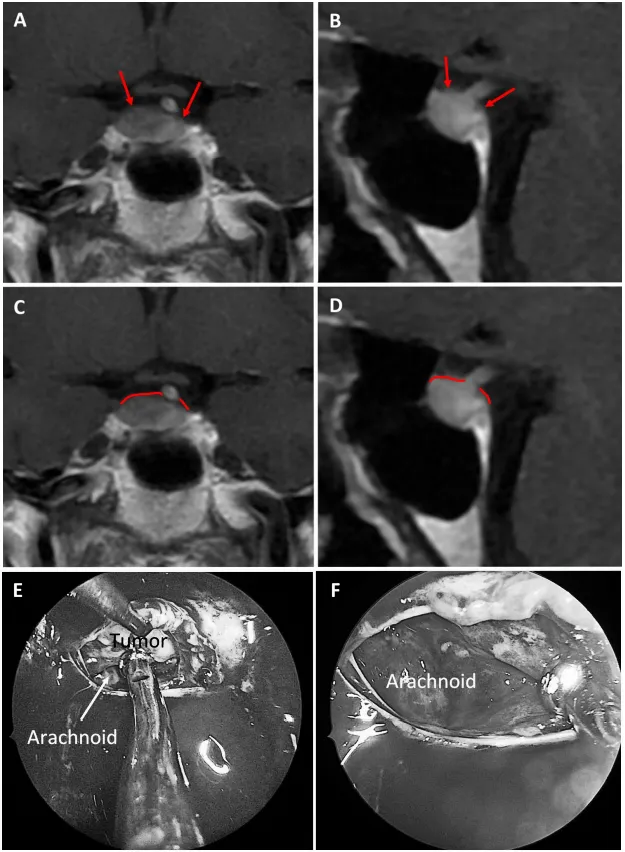

2混合型鞍隔屏障案例

圖5

圖5:56歲女性ACTH腺瘤患者。a、b術(shù)前MRI:黃色箭頭指示厚度大于1毫米的強化屏障區(qū),紅色箭頭指示厚度小于1毫米的薄弱屏障區(qū)。c、d術(shù)前MRI:黃色標記線標示強韌屏障區(qū)域,紅色標記線標示薄弱屏障區(qū)域。e術(shù)中圖像:可見由垂體腺與蛛網(wǎng)膜共同構(gòu)成的混合屏障結(jié)構(gòu)。